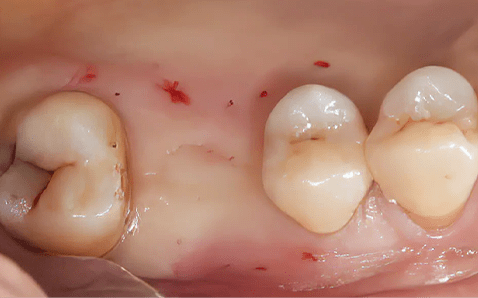

Case 01

임플란트 식립 전 절개없는 임플란트 식립 직후

촬영시기 : 2024.12.05